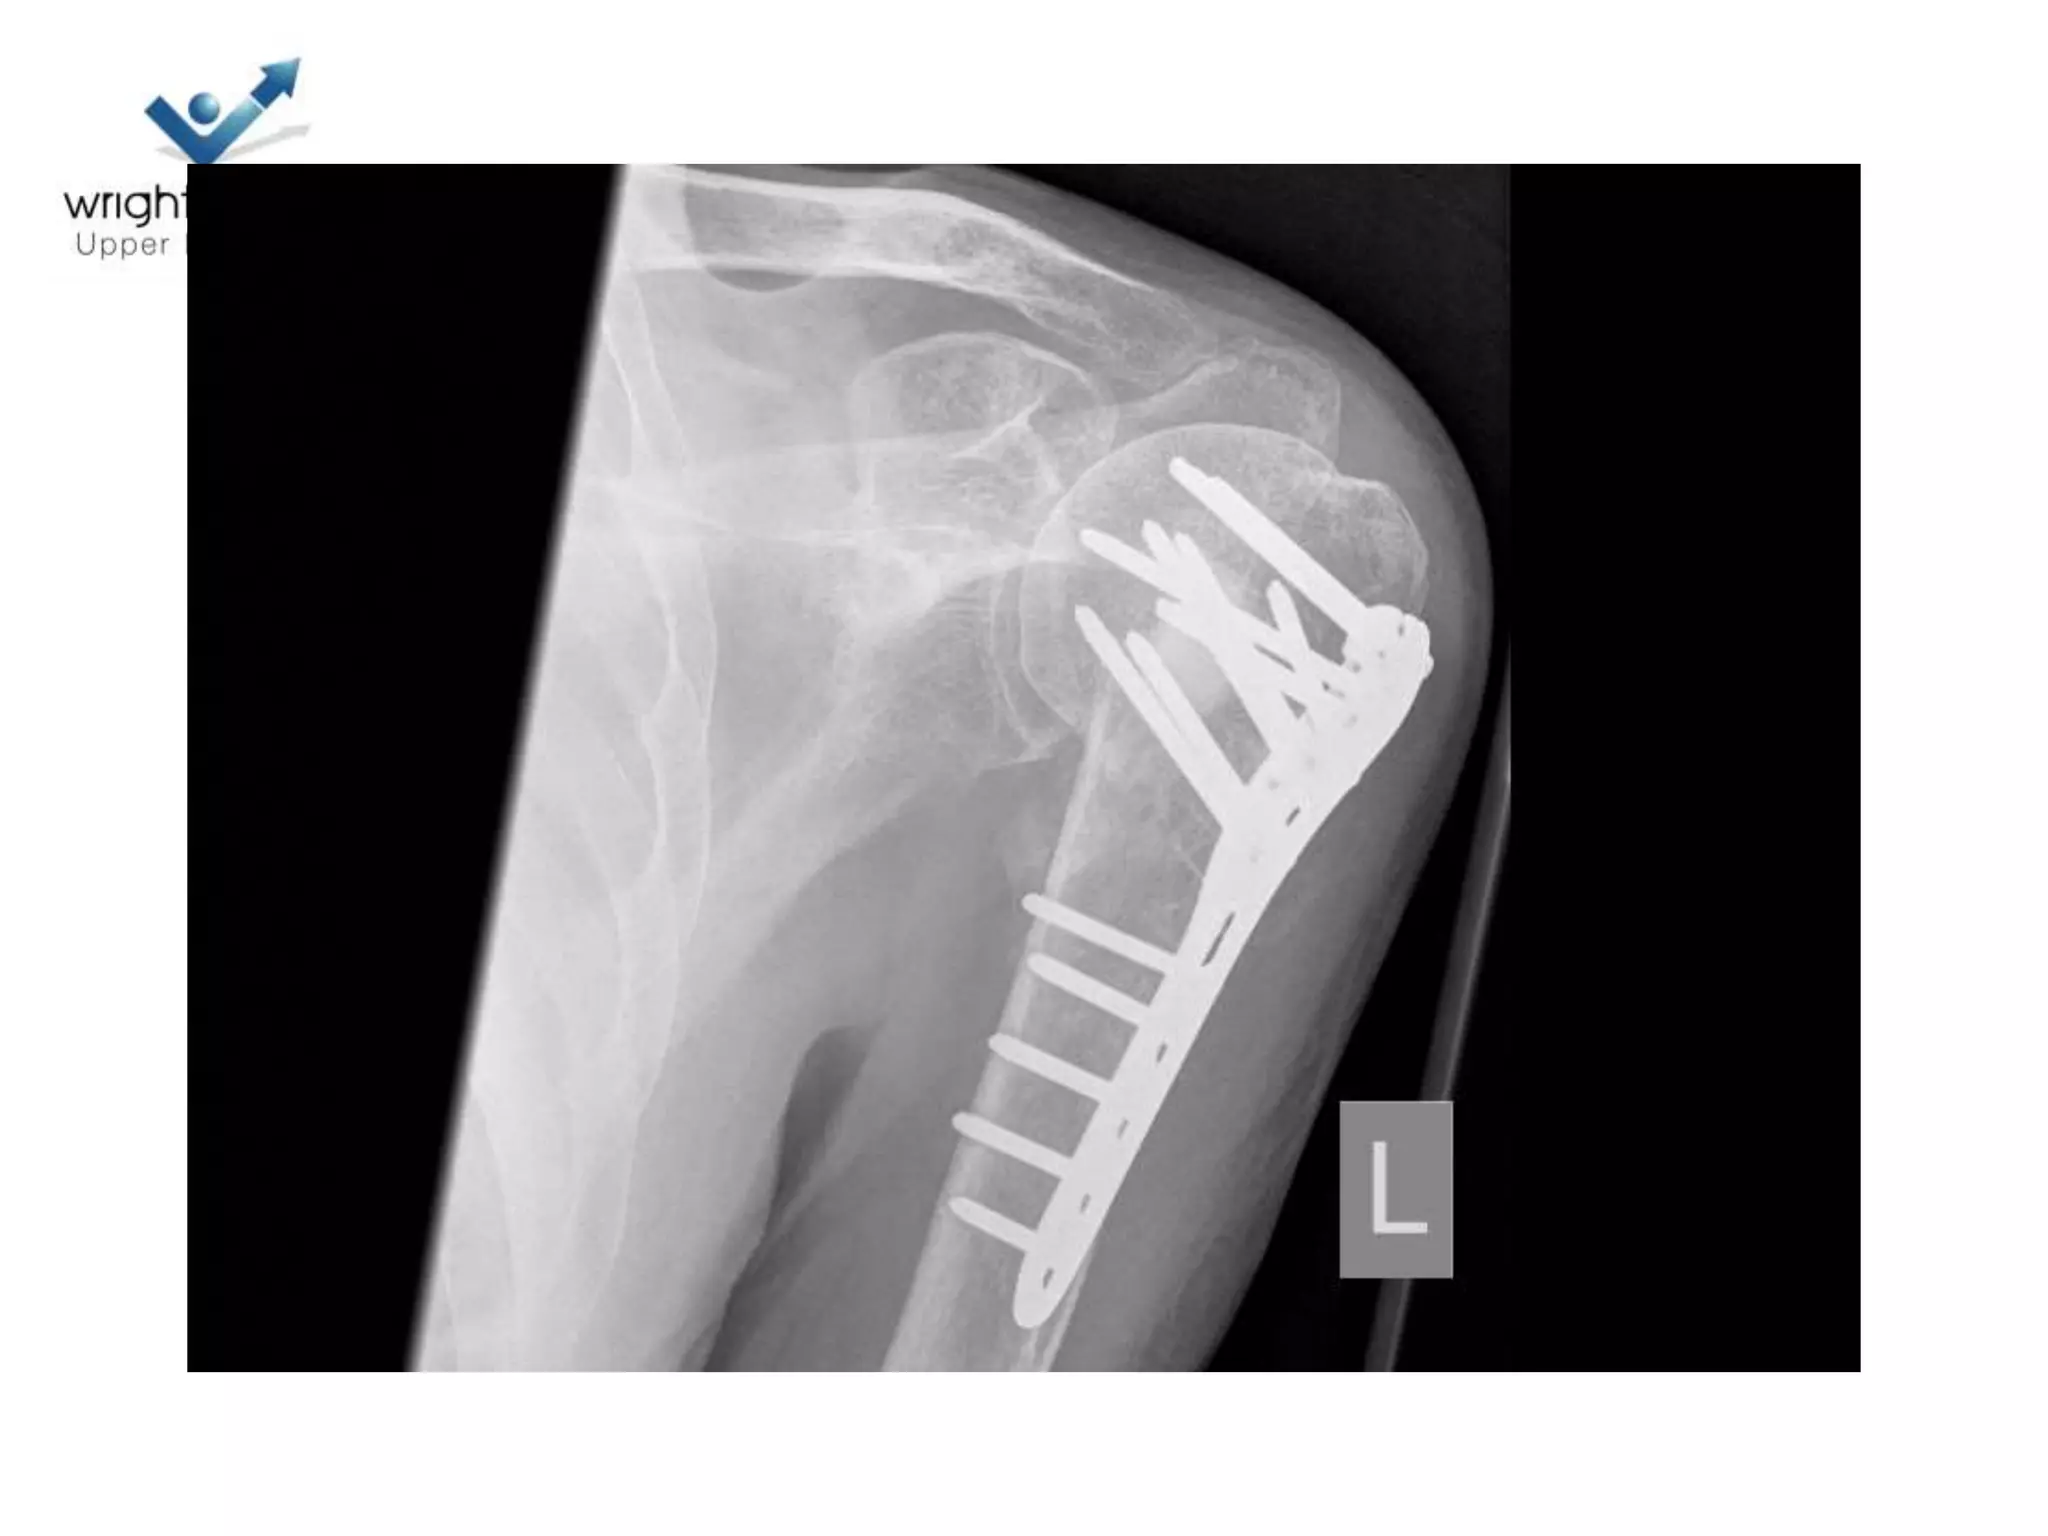

Locking plate; Tips

Locking plates: Tips

Locking plate: Tips